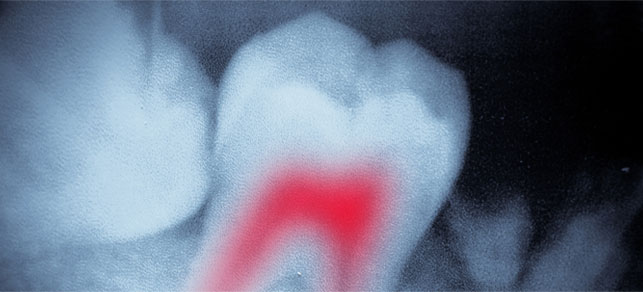

ROOT CANAL THERAPY - ENDODONTICS​

An endodontic treatment saves a severely injured, cracked, or decayed tooth when its pulp becomes inflamed or infected. If it is not treated promptly, pain or a tooth abscess results. Endodontic treatment is also known as a "root canal."